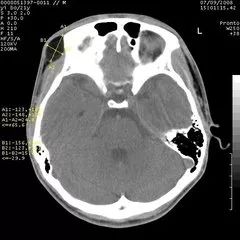

CT头颅扫描图像

从“计算机体层摄影”这个名词可以看出,CT实际上也是一种体层摄影,但它在成像技术上却有了突破性进展。它有了完善的扫描机架,扫描角度极大提高,轻易地实现了横断面的体层摄影。更突出的是,CT首创性地将高性能计算机技术应用到影像领域,又使用高性能的探测器同步检测X线衰减信息,影像精度空前提高,层面结构清晰,完全消除了重叠对病变遮盖的问题。更难能可贵的是,CT能调节“窗宽、窗位”等手段(后续再介绍,也可参阅我写的科普专著),使密度分辨力得到了空前的提高,原本在密度对比方面差别很小的器官组织,也可以在CT上显示出浓淡不同的清晰影像。比如,针对头颅,CT不仅能够看清颅骨的结构,而且能够看到大脑的内部结构如灰质、白质和脑室等。因此,CT极大地拓宽了X线诊断的适用范围。